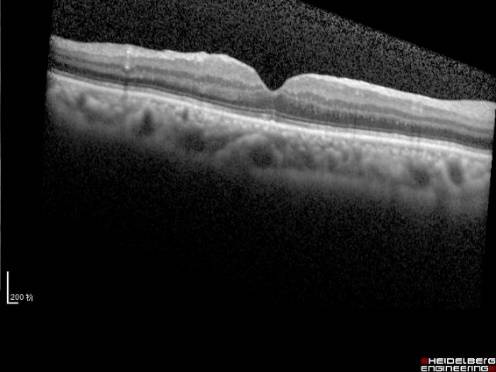

黄斑前膜

黄斑区的结构细微精细,其表面还有玻璃体后皮质和视网膜内界膜,有的时候,在后皮质和内界膜之间,会增殖产生一种特殊的病理性膜结构,叫黄斑前膜(见图10)。这层膜结构,与内界膜紧相连,同时也和玻璃体的后皮质紧密相连,当膜的增生,加上玻璃体的牵拉,使得黄斑被牵拉起来,于是产生视物的变形、视力降落。一旦产生了上述症状就需要及时通过玻璃体手术剥除增殖膜阻止视力的恶化,手术时间短,并发症少,大多数患者视力保持稳定,部分患者视力逐步提高。

图10. 黄斑前膜